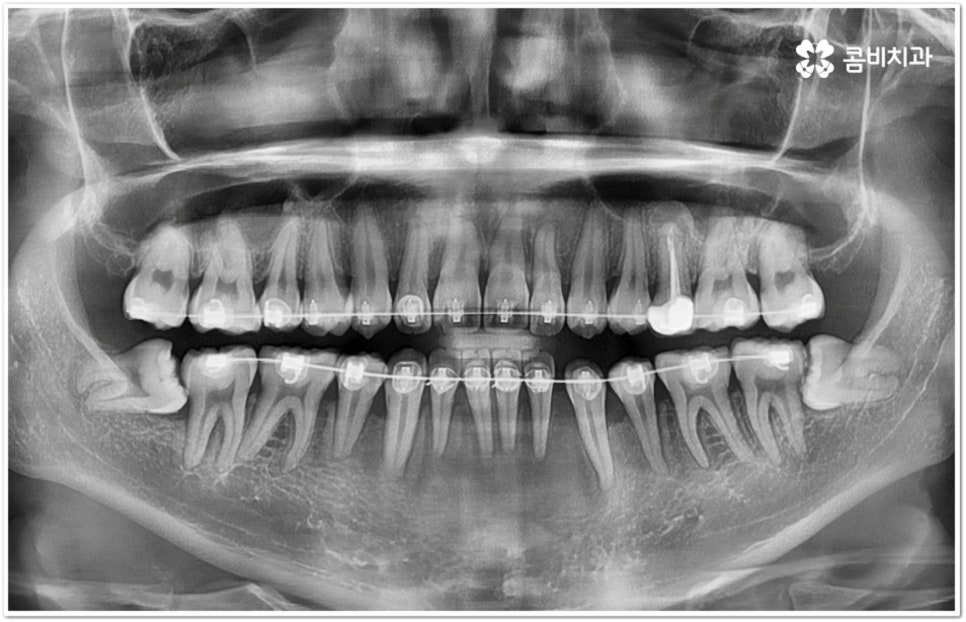

만약 똑바로 자라나고 관리가 용이하며 마주보는 대합치 역시 정상적으로 맹출되었다면 사랑니를 꼭 발치할 필요는 없을 거예요. 그러나 보통 사랑니는 사람의 치아 중에 가장 마지막에 나오는 치아라서 이미 구강 내 공간이 비좁은 상태이기 때문에 비스듬하게 자리를 잡고 일부분만 맹출이 되는 경우가 많이 있어요. 보통 머리가 앞쪽으로 기울어진 근심위로 자리잡는 케이스가 가장 많으며 그 밖에도 치아 머리가 뒤쪽으로 기울어져 있거나 혀쪽, 볼쪽으로 누운 케이스, 아예 옆으로 완전히 누운 케이스 등도 발견되고 있는데요.

잇몸에 반쯤 덮힌 채로 삐뚤게 나온 사랑니는 칫솔질을 제대로 하기 어렵고 위생 관리가 잘 되지 않아 주변 잇몸에 염증이 생기기 쉬우며 어금니까지 충치가 번질 위험이 높아지게 되어 구강 건강 관리 및 예방 차원에서 발치 처치를 해주실 필요가 있어요. 발치 난이도는 사랑니의 경사 각도와 방향 및 치아 뿌리의 길이와 개수, 사랑니 뒤쪽 턱 뼈의 각도 및 형태, 하치조 신경 또는 상악동까지의 거리 등에 따라서 달라질 수 있습니다.

이때 아래사랑니발치 의 경우 아래턱 부근을 지나가는 큰 신경인 하치조 신경을 건드리지 않고 조심스럽게 사랑니만 제거해야 하기 때문에 3D-CT 등 정밀 검진 기계를 통해 사랑니의 매복 위치, 깊이, 각도 등의 상태와 신경까지의 거리 등을 먼저 꼼꼼하게 파악한 후에 발치를 해 줄 필요가 있는데요. 만약 완전히 매복되어 있다면 사랑니 주변에 함치성 낭종이 발생할 수도 있는데 이로 인해 주변 치조골이 파괴되고 어금니 쪽으로 병변이 확산되면 결국 치아를 상실하게 되거나 턱뼈가 약해져서 작은 충격에도 부러지는 현상이 발생할 가능성도 있으므로 될 수 있는대로 치료 시기를 놓치지 않는 것이 중요한 포인트라고 할 수 있어요.

아래사랑니발치 와 다르게 윗 사랑니 발치 시에는 상악동까지의 거리가 너무 짧을 경우 천공 및 감염의 위험이 있으니 이에 대해서 3D CT 를 통해 꼼꼼하게 확인하고 환자분들의 상황에 맞는 치료를 진행할 필요가 있어요. 예를 들어 사랑니로 인한 문제가 크지 않은 경우 그대로 두고 지켜볼 수도 있고 다른 치료를 하는 중에, 즉 교정이나 임플란트 등을 진행하는 과정에서 발치가 꼭 필요한 경우라면 상악동 거상술, 뼈이식 등의 치료를 선행하여 무리하지 않게 뽑아주는 것이 좋을 거예요.

교정 치료를 하기 전에 사랑니를 먼저 발치해야 하는지 문의주시는 분들이 있는데 이 역시 검진 후에 환자분들의 상황에 맞게 결정하는 것이 좋기 때문에 교정과 사랑니 발치에 두루 임상 경험이 풍부하신 의료진을 선택하시면 치과를 옮겨다니는 번거로움 없이 보다 편안하게 적기에 필요한 치료를 받으실 수 있습니다. 또한 처음부터 끝까지 책임지고 철저하게 케어해 주는 치과의 도움을 받으시면 업무 때문에 많이 바쁘신 직장인 분들의 경우 시간을 단축시킬 수 있어 좋을 뿐 아니라 환자분들이 느끼실 수 있는 여러가지 심적인 부담도 덜 수 있을 거예요.